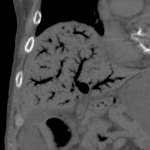

Age: 97

Sex: Male

Indication: Abdominal pain, hypotension

Sample ReportExtensive pneumatosis involving the stomach, small bowel, and large bowel with portal venous gas concerning for bowel ischemia. No pneumoperitoneum. Pneumatosis extends from the stomach into the lower thoracic esophagus.

Left upper pole renal neoplasm with likely metastatic lesions involving the right iliac wing, left pubic root and superior pubic ramus, and left inferior pubic ramus with associated pathologic fractures and periosteal reaction.

Right mesenteric mass, ill-defined para-aortic nodal tissue, and enlarged left inguinal node could represent additional sites of metastatic disease or could relate to a second primary neoplasm. Given the relative transition point in small bowel caliber near the right lower quadrant mesenteric mass, small bowel obstruction as an inciting factor for bowel ischemia is a consideration.